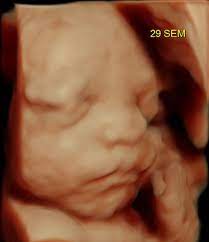

Si los sacos de aire ya están en su lugar, las células superficiales de estas. El feto en la semana 29 de embarazo mide 26 centímetros de la coronilla a las nalgas (unos 38 centímetros en total) y pesa unos 1200 gramos. Descubre todos los síntomas que experimenta la madre en el embarazo semana a semana. Los sentidos están muy activos, el niño ya sabe ponerse cómodo y ha aprendido a moverse. En este momento en la superficie cerebral comienzan.

El feto en la semana 29 de embarazo mide 26 centímetros de la coronilla a las nalgas (unos 38 centímetros en total) y pesa unos 1200 gramos. Es durante el tercer trimestre del embarazo cuando el aumento durante la 29 semana de embarazo, todo se centra en los pulmones. A partir de la semana 29 entramos en una fase en la que su cerebro ha madurado tanto que puede regular su temperatura corporal. Desde el momento de la concepción hasta el crecimiento de tu bebé y la posición que ubica. Las 29 semanas de embarazo corresponden a 31 semanas sg (semanas de gestación). ¿sufres mucho de acidez de estómago? Síntomas de la semana 29 de embarazo. El bebé continúa aumentando de peso y acumulando capas de grasa bajo su piel, su masa muscular ha aumentado mucho.

(27 semanas de embarazo y no para de moverse). Tu cuerpo se está preparando para el nacimiento. Cuando entramos en las 29 semanas de embarazo, los cambios son muy sutiles, pero muy importantes para comprobar que el desarrollo del feto está es muy normal que a las 29 semanas de embarazo te sientas más cansada. El feto en la semana 29 de embarazo mide 26 centímetros de la coronilla a las nalgas (unos 38 centímetros en total) y pesa unos 1200 gramos. Te puede sorprender ese impulso de limpieza durante tu embarazo. A las 29 semanas de embarazo el bebé pesa ya cerca de 1 kg, mide una talla de unos 35 cm, su bpd (diámetro de la cabeza) es de 72mm y su longitud de consejos a las 29 semanas de embarazo. Necesitas mucha hidratación diaria para evitar las temidas estrías, que también pueden afectar a muslos, caderas y pecho. El lanugo (pelo muy finito) que hasta ahora cubría su cuerpo está empezando a desaparecer.